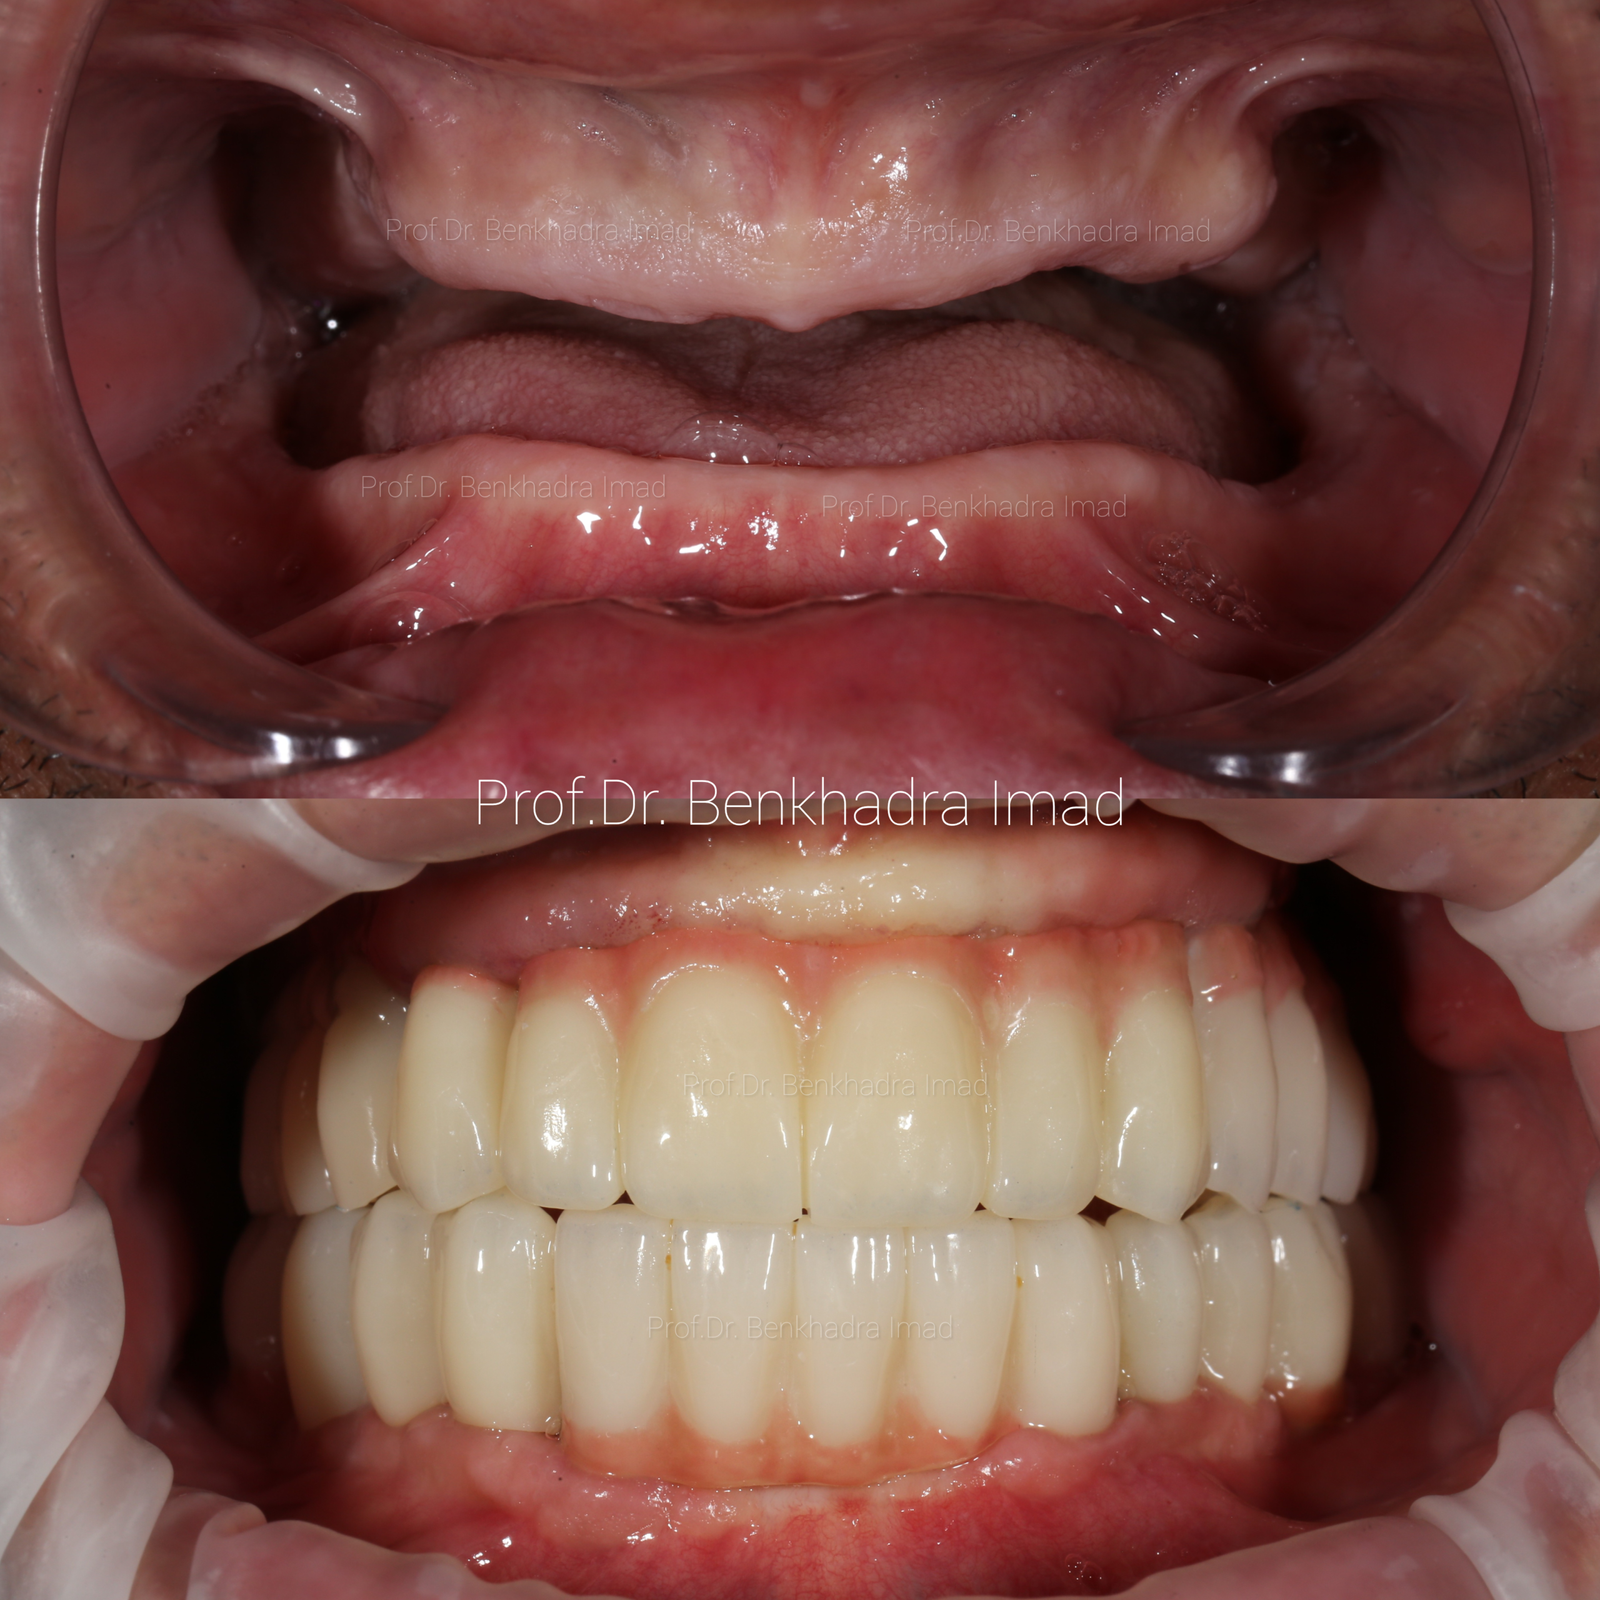

Full Smile Rehabilitation with Dental Implants | Real Case